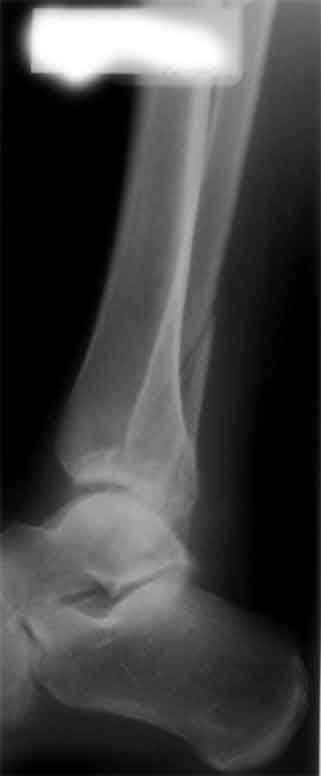

Здесь представлено решение похожей проблемы. Больной в течение года лечился консервативными мерами, и боли в голеностопе были основным показанием к операции.

Проведена обычная стандартная процедура по исправлению неудовлетворительного состояния голеностопного сустава, где кроме удлинения малоберцовой с применением compression tension device за проксимальный конец пластины, проведено замещение трикортикальным графтом из крыла, освобождение синдесмоза и медиальной щели от

фибротических масс с фиксацией.

Дополнительно у больного плоская стопа, во время операции провели небольшую скользящую остеотомию, надеемся, что поможет.